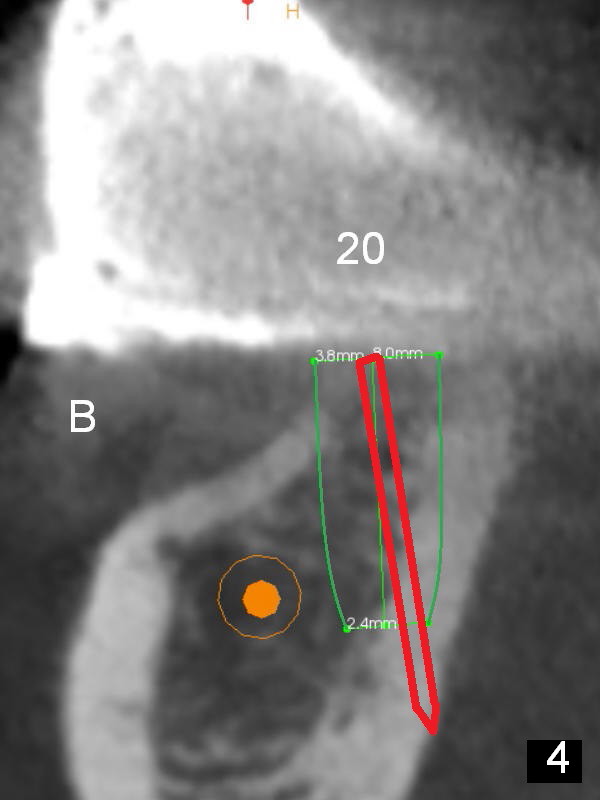

At the site of #20, osteotomy for the same implant is finished without sign of nerve injury or lingual plate perforation. To place the implant a little deeper, a 2 mm drill is used to deeper for another 2 mm. The latter also turns out to be hard. When it is done, perforation occurs, noticed first by the patient (Fig.4). The perforation is fixed with Osteogen plug (Fig.5 white area), while the implant is placed at the crestal level as planned.